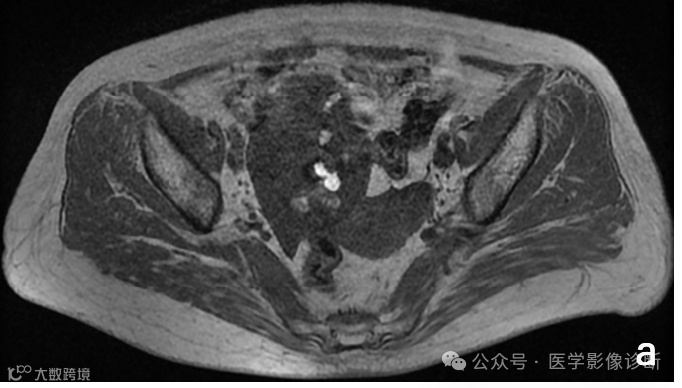

胰腺尾部占位性病变,轴位MRI T1WI (a)、T2WI/FS (b)、T1WI/FS (c)、增强(d)序列均显示病变信号与脾脏相似,但是放射医生诊断为相对常见的胰腺神经内分泌肿瘤,而非罕见的异位脾脏。手术病理证实为胰腺内异位脾脏。